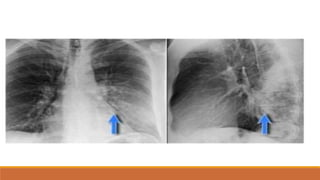

TRÀN KHÍ MÀNG PHỔI

• PHIM ĐỨNG:

• VÙNG SÁNG VÔ MẠCH NẰM NGOÀI LÁ TẠNG

• ĐƯỜNG MỜ CỦA LÁ TẠNG BAO BỌC NHU MÔ PHỔI XẸP

• TKMP ÁP LỰC: ĐẨY TRUNG THẤT VỀ ĐỐI BÊN, XẸP PHỔI THỤ ĐỘNG,VÒM

HOÀNH DẸT, RỘNG KHOẢNG LIÊN SƯỜN

TKMP TƯ THẾ ĐỨNG

TKMP ÁP LỰC